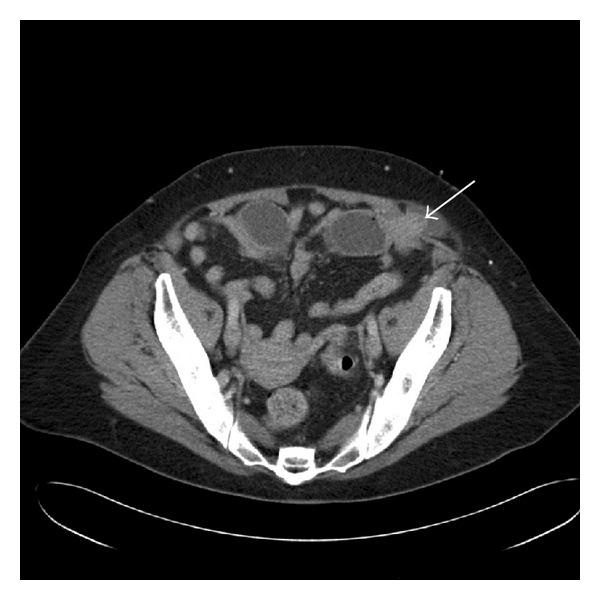

A spigelian hernia is a protrusion through an anterior abdominal wall defect along the linea semilunaris. The traditional method of repair consists of an open surgical technique requiring a lengthy abdominal incision to allow visualization of the defect. However, with the emergence and availability of laparoscopic techniques, a minimally invasive approach is feasible. Only eight prior case reports have documented emergent laparoscopic repair of a spigelian hernia. We describe the first successful laparoscopic repair of a spigelian hernia in an emergent setting at our institution.

半月线疝是指通过腹前壁沿半月线的缺损处突出。传统的修复方法是采用开放手术技术,需要做一个长的腹部切口以便观察缺损部位。然而,随着腹腔镜技术的出现和应用,微创方法是可行的。此前仅有8例病例报告记录了半月线疝的急诊腹腔镜修复。我们描述了在我们机构急诊情况下首例成功的半月线疝腹腔镜修复。